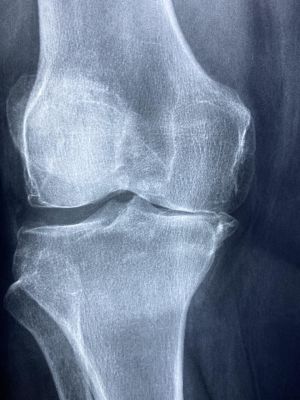

Řídnutí kostí neboli osteoporóza patří mezi nejčastější civilizační onemocnění.

Je to nemoc ekonomicky velmi nákladná, protože vede ke ztrátě soběstačnosti a pohyblivosti, zejména u starších lidí. Může zabíjet — ztráta hybnosti je rizikovým faktorem pro předčasná úmrtí. Zrádnost osteoporózy spočívá v tom, že dlouho nevyvolává příznaky ani nebolí, prvním projevem může být zlomenina nebo komprese obratlů a deformity páteře.

Kostní hmotu budujeme především během dětství, ale kvalitu svých kostí ovlivňujeme celý život. Řídnutí kostí v souvislosti se zvyšujícím se věkem není nevyhnutelné. Kost je metabolicky aktivní, neustále se tvoří a odbourává. Hustota kostí záleží na tom, který proces převažuje. Osteoporóza je důsledkem vyššího odbourávání kosti než jejího budování.